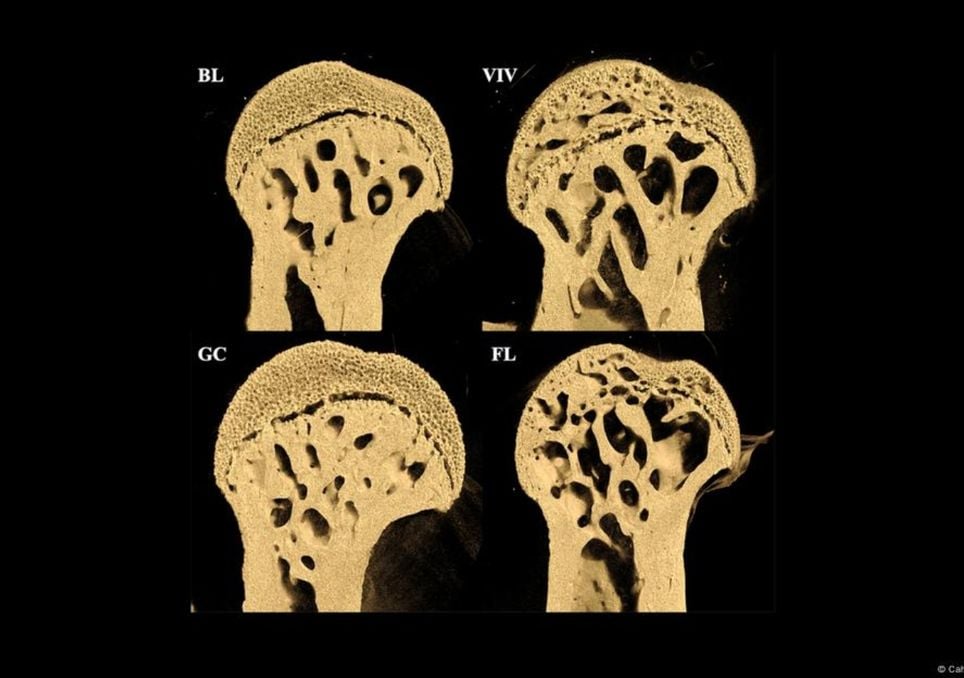

Los resultados sorprendieron a los científicos: después de 37 días los huesos de los animales mostraron llamativas alteraciones estructurales. Encontraron que los huesos que normalmente soportan carga -como los fémures- son los más afectados.

Tras poco más de un mes en órbita, los investigadores detectaron una marcada degradación ósea en las patas traseras de los roedores, con amplias cavidades que evidencian pérdida de densidad mineral.

El análisis reveló un patrón curioso: mientras los huesos de soporte sufrían un deterioro acelerado, estructuras como la columna lumbar o el cráneo permanecían prácticamente estables. De hecho, algunas zonas del rostro y la mandíbula mostraron una ligera ganancia de densidad.

“La tomografía microcomputarizada y los análisis histológicos de los huesos de ratones que volaron al espacio en la EEI durante 37 días en el experimento Rodent Research-1 de la NASA muestran una pérdida ósea cortical y esponjosa específica del sitio significativa que ocurre en el fémur, pero no en las vértebras L2”, sostiene el trabajo, que se publicó en la revista PLOS ONE.